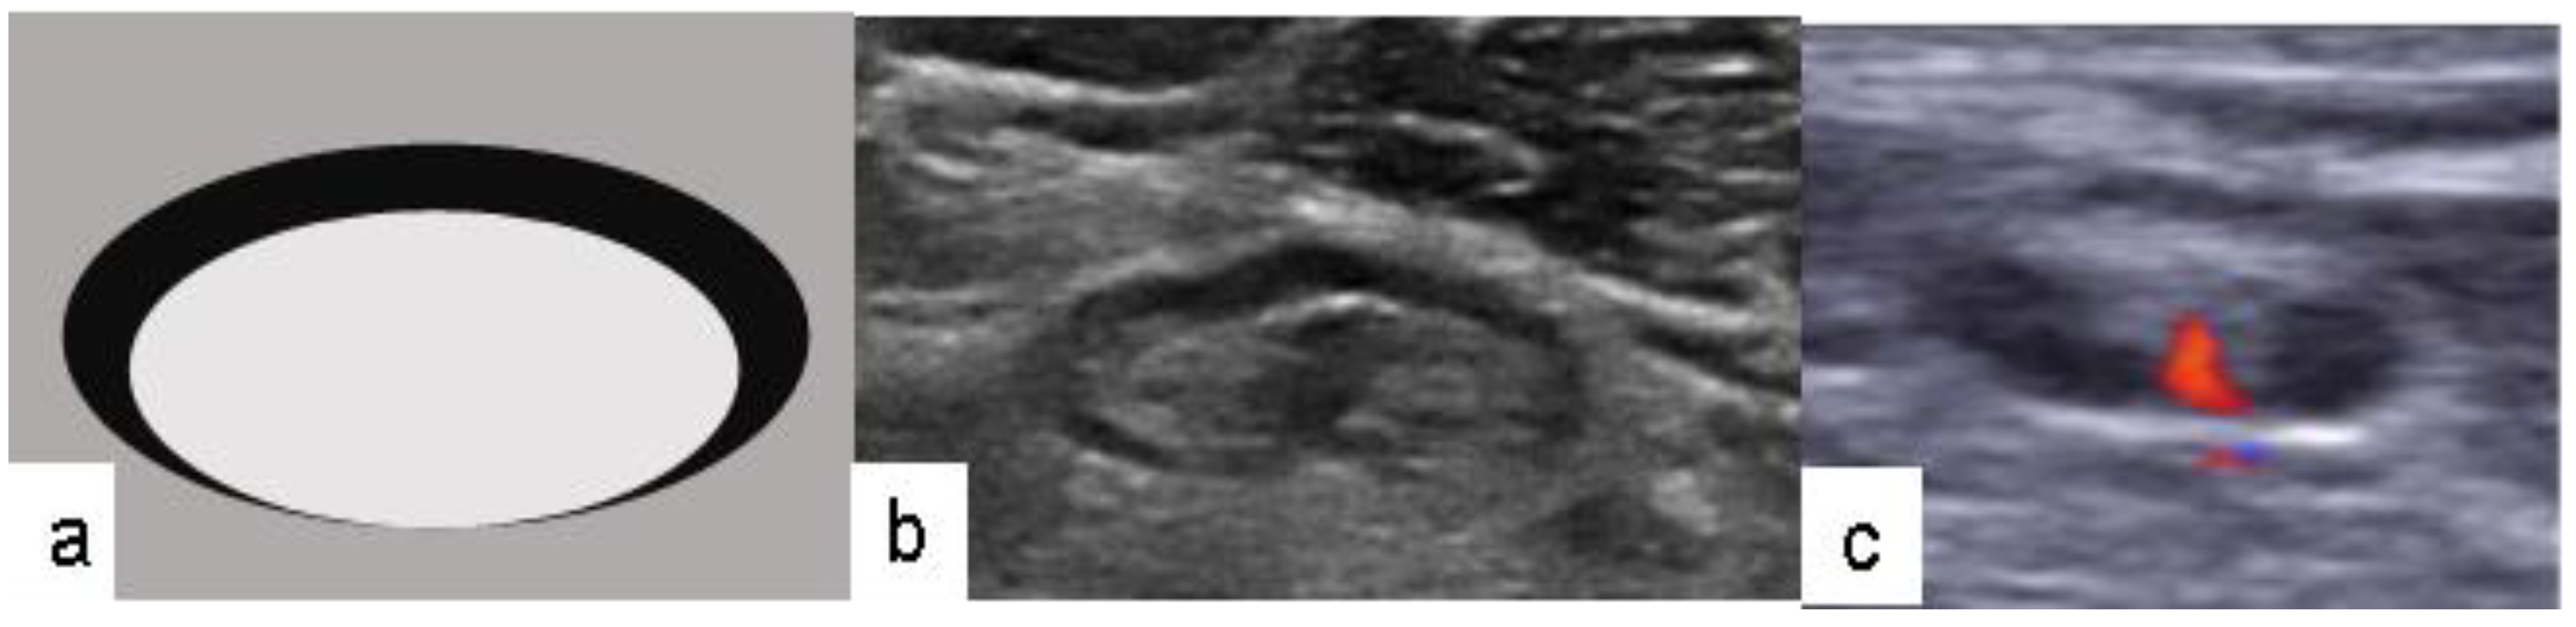

- Ecanow, J.; Abe, H.; Newstead, G.M.; Ecanow, D.B.; Jeske, J.M. Axillary Staging of Breast Cancer: What the Radiologist Should Know. Radiographics 2013, 33, 1589–1612. [Google Scholar] [CrossRef]